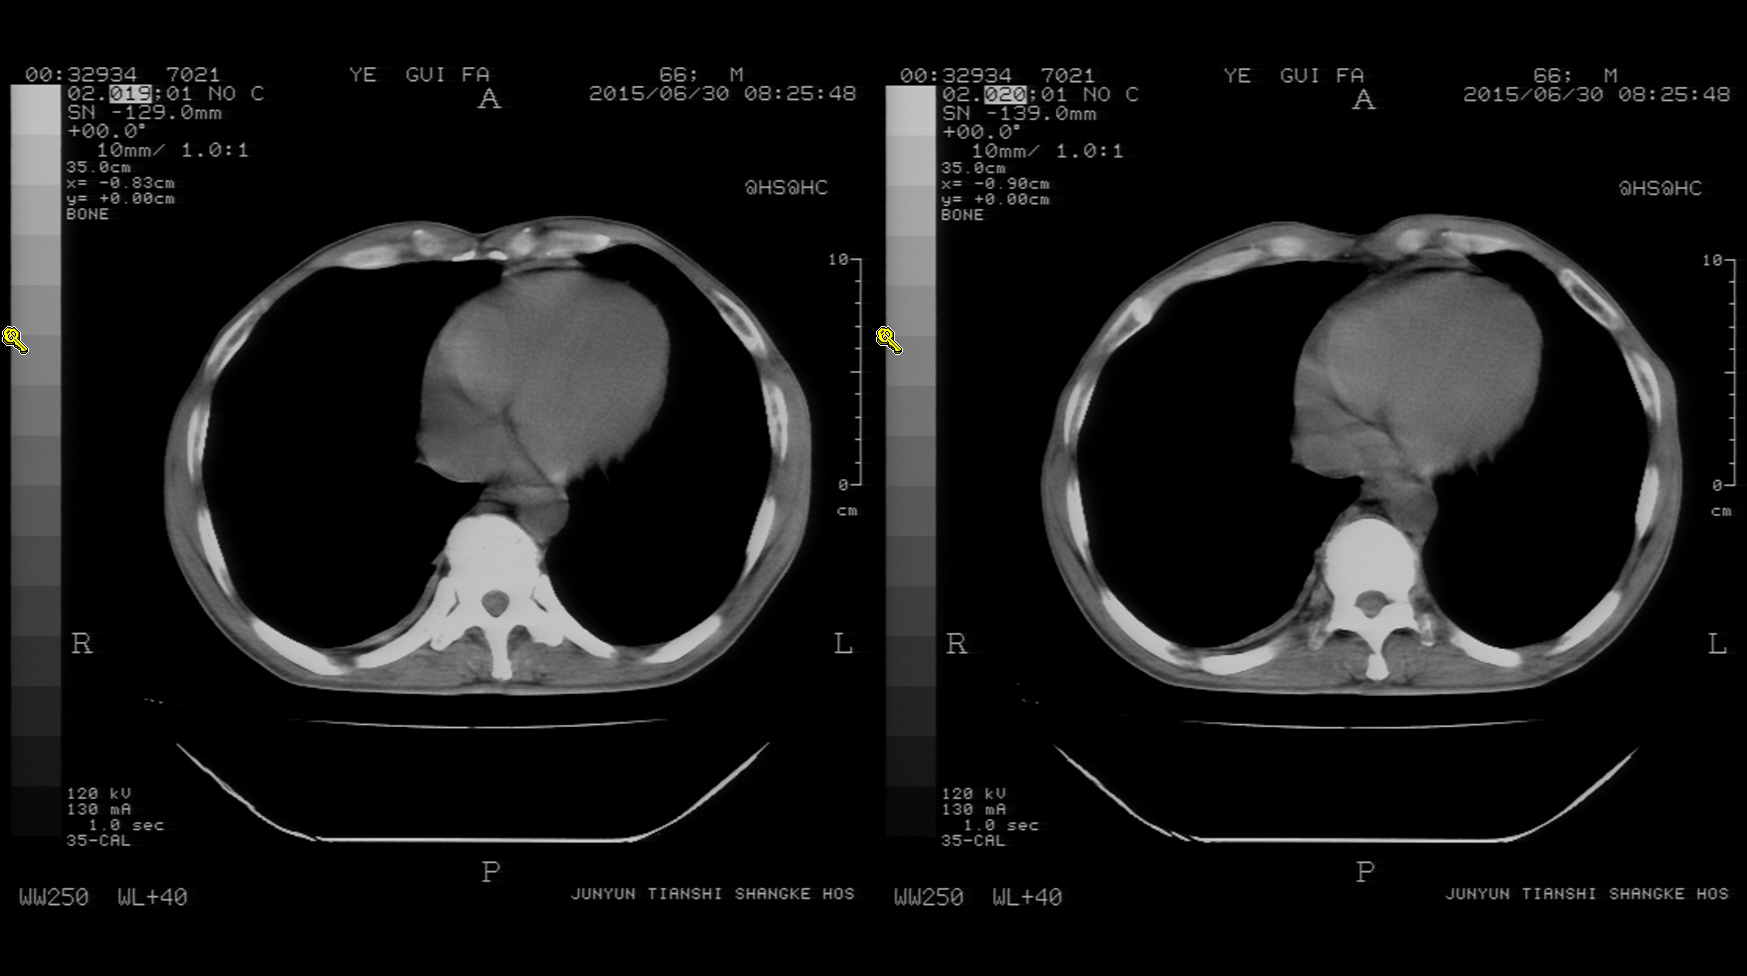

CT50766:各位老师帮看一下

本帖最后由 cefcmj 于 2015-6-30 18:40 编辑 男性 66岁 体检 自诉胸部无明显不适 既往抽烟10年余 ...

右下肺隔离症?建议增强。

右下肺隔离症?